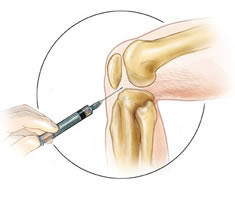

Some of our doctors have been trained in the use of musculoskeletal ultrasound.  This is an imaging method that does not use X-rays and allows your specialist to visualize the inflamed joints, tendons and bone structures.  Ultrasonography allows the physician to direct a needle into a joint, bursa, or other fluid collection in order to remove fluid or provide a therapeutic injection.

If necessary, we may also perform anesthetized removal of joint fluid (arthrocentesis) for fluid analysis and  microscopic examination including crystal analysis.  We also interpret bone density (DEXA) testing in light of comorbidities and medications and can send a detailed osteoporosis report including recommendations to your primary care physician.